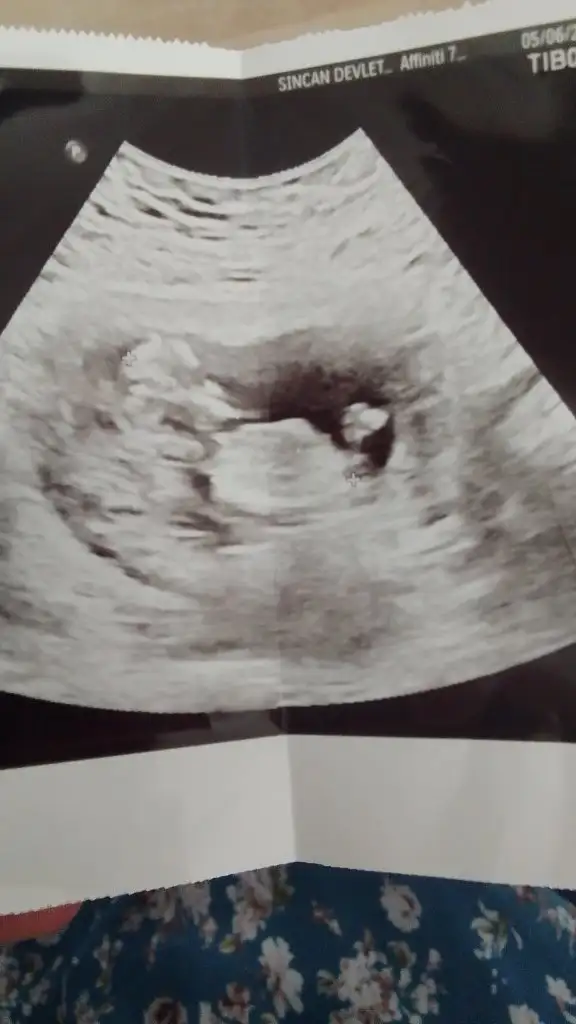

Nub’a göre yorum yapmak için bacak arasında nub kısmının görünmesi gerek. Yukarıdaki görüntüde diğer kızların pipi dediği şey nub. Bu teoriye göre nub yere paralelse kız, havaya doğru açı yapıyorsa erkekmiş. Sizde o kısmı göremediğimden yorum yapamadım

Teşekkür ederim sağlık olsunNub’a göre yorum yapmak için bacak arasında nub kısmının görünmesi gerek. Yukarıdaki görüntüde diğer kızların pipi dediği şey nub. Bu teoriye göre nub yere paralelse kız, havaya doğru açı yapıyorsa erkekmiş. Sizde o kısmı göremediğimden yorum yapamadım

Ya aslında iyi biliyorum ama kendimde olunca kuşkuya düştüm bir an tahminim oğlum da tutmuştu nuba göre bakalım bunda da nuba göre kız gördüm belki bilen başkası olursa diye paylaşıyorum bu cumaya tekrar gidecem bakalimAmin hepsi sağlıklı olsun bebişlerimizin, cinsiyeti de merak ediyor tabi insan. Ben de çok sabırsızım. Tüm teorileri araştırdımbelki içimizde cinsiyeti belli olanlar nub teorisi tutmuş mu diye bize yorum yapabilir

Teoriye göre benim ki belli mi? Yani bir tahmin ?Amin hepsi sağlıklı olsun bebişlerimizin, cinsiyeti de merak ediyor tabi insan. Ben de çok sabırsızım. Tüm teorileri araştırdımbelki içimizde cinsiyeti belli olanlar nub teorisi tutmuş mu diye bize yorum yapabilir

Görünen nub ise kız gibi :) sağlıklı oldunTeoriye göre benim ki belli mi? Yani bir tahmin ?